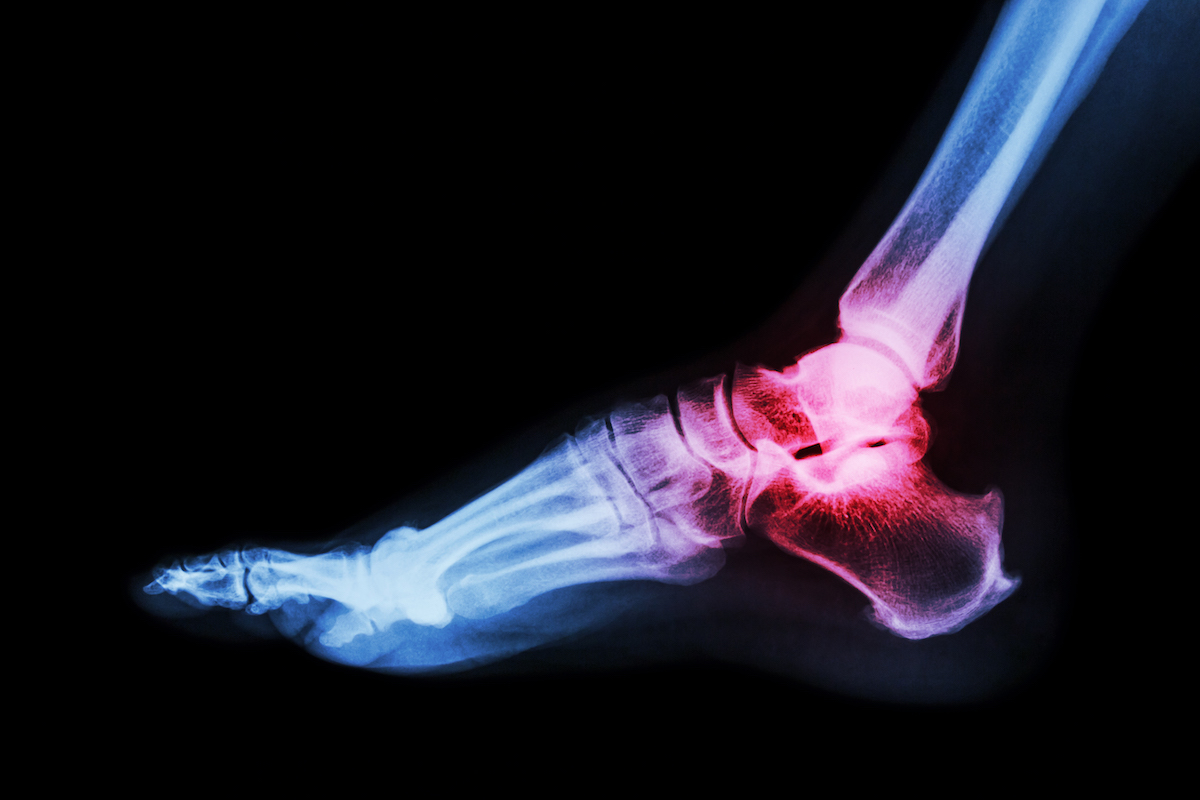

At Canyon Foot and Ankle, Dr. Levi Berry provides expert treatment for foot and ankle fractures and trauma, helping patients find fast relief from pain, swelling, and limited mobility. Fractures and traumatic injuries can occur from sports, accidents, or everyday activities, often leading to significant discomfort and difficulty walking. Left untreated, these injuries can worsen, causing improper healing or long-term complications that interfere with daily life. Serving the Spanish Fork, Utah community and surrounding areas, Dr. Berry uses proven techniques and advanced care methods to stabilize injuries, promote proper healing, and restore strength so patients can return to their normal activities safely and effectively.

Dr. Levi Berry is committed to providing personalized care for patients of all ages dealing with foot and ankle fractures or traumatic injuries in Spanish Fork, Utah. Whether caused by sports accidents, falls, or sudden impacts, fractures and trauma can be both painful and debilitating. At Canyon Foot and Ankle, patients receive a thorough evaluation, customized treatment, and guidance throughout the recovery process to ensure proper healing and reduce the risk of long-term complications. With a focus on restoring strength and mobility, Dr. Berry ensures that each patient leaves not only on the path to recovery but also with the knowledge and support needed to protect their foot and ankle health moving forward. Schedule your appointment today and take the first step toward lasting healing.